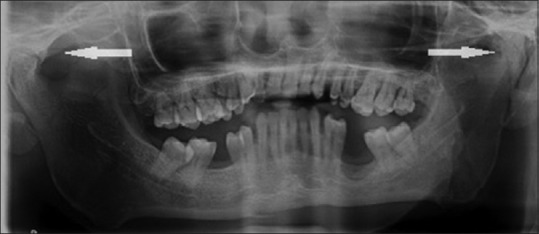

1. Radiographs:

– OPG

OPG: *Helps in bilateral comparison of the joint.**The antigonial notch can be appreciated in this type of radiograph.

• Decreased ramus height on the affected site.

• Lack of joint space.

• Normal joint space obliteration by bone/fibrous growth.

• Elongation of coronoid process.

• Deep antigonial notch.